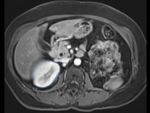

| fixed image/target intra-op CT |

moving image pre-op MRI |

| MR/CT before registration (click to enlarge) | |

| MR/CT after fiducial rigid alignment (click to enlarge) |